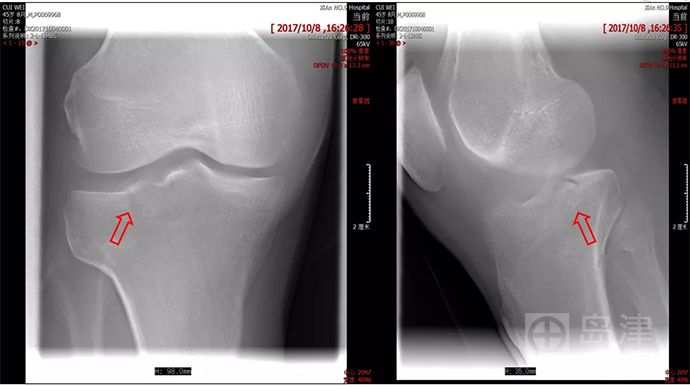

病例三:骨折征象显示

45岁男性,与孩子玩耍时,从一级台阶上蹦下即感右膝疼痛明显,无法行走。

右膝正侧位X线:未见骨折直接及间接征象 。

DTS 显示胫骨平台骨折 。

查 CT MR ,与DTS结果一致。

隐匿性骨折 DR无法发现

右胫骨平台隐匿性骨折

DTS可发现平片无法发现的骨折

CT结果与DTS一致

MRI结果与DTS一致

图像来源:西安市第九医院